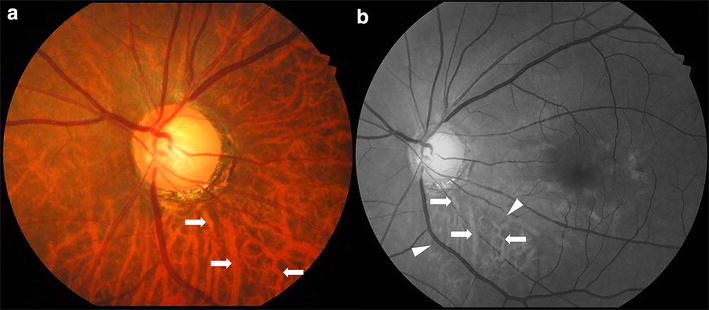

The main theories regarding glaucoma pathogenesis stress the importance of optic nerve head (ONH) vascularization. The peripapillary choroid provides the main blood supply to the prelaminar region of the ONH [1]. As perfusion anomalies contribute to glaucoma [2], several studies suggest that peripapillary choroidal thickness (PPCT) could potentially serve as a clinical indicator for diagnosing glaucoma [3,4,5].

In many cases, however, ONH analysis is difficult due to features such as a tilted position, a complex distribution of ONH margins, or the presence of drusen or myopic crescents. In these and other situations, supplementary tests such as PPCT analysis could greatly benefit the clinician [6].

The first OCT analysis evaluating choroidal thicknesses in eyes with and without glaucoma was focused within the macular area, and again discrepancies over choroidal thinning in glaucomatous eyes are reported [21,22,23,24]. It seems that studying the foveal, temporal, nasal macular, or average macular choroidal thicknesses is not the best approach for evaluating glaucomatous changes [15, 16].

PPCT examination seems to be the most useful approach to diagnosing glaucoma [3,4,5]. But relationship between PPCT and blood supply is still controversial in the available literature. In the Beijing Eye Study [2], the findings do not indicate a significant association between PPCT and blood pressure (BP). Gupta et al. [12], using novel automated choroidal segmentation software in an Asian population did not find any association between BP and PPCT either. However, in a recent review performed by Goharian and Sehi [25], the conclusion was that alterations in BP and ocular perfusion pressure could affect choroidal thickness. Tan et al. [26] report that arterial BP had an effect on subfoveal choroidal thickness. New studies are necessary to elucidate the relationship between BP, choroidal thickness and IOP. These studies need to conduct different measurements during the same day of these factors while keeping strict control of vascular factors. With regard to the profile of the PPCT, our finding of the thinnest PPCT in the inferior region is consistent with other studies. Thus, we believe this area with a thinnest choroid may represent consequently an area of lower blood supply (as the peripapillary choroid is the main source of ONH nourishment), which may predispose the inferior region of the optic nerve to glaucomatous ischaemic damage [27, 28].